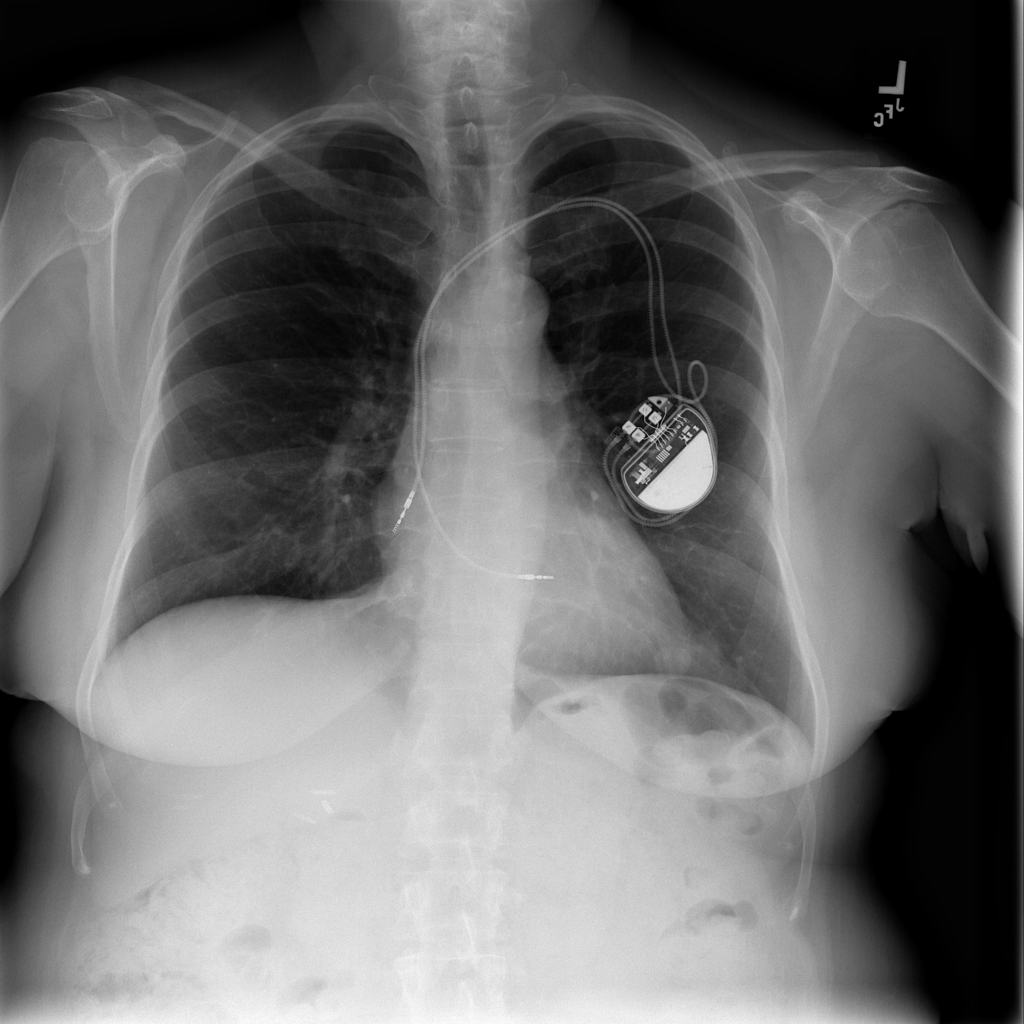

Nodule

A nodule is a small rounded opacity in the lung or chest field. It is a descriptive imaging finding that can be benign or more concerning depending on size, appearance, and context.